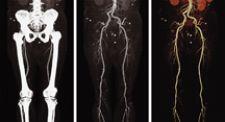

Visage CS is built on the thin client/server software architecture from Visage Imaging Inc., reportedly delivering unmatched performance for very large datasets such as CT runoffs, multiphase CT angiography studies and cardiac CT. All functionality becomes available on standard client PCs throughout the entire enterprise network via LAN, WAN, or Internet. Visage CS is fully scalable from small systems to large, clustered solutions that support virtually any number of concurrent users and any storage size, while still maintaining a single central database, according to the company.